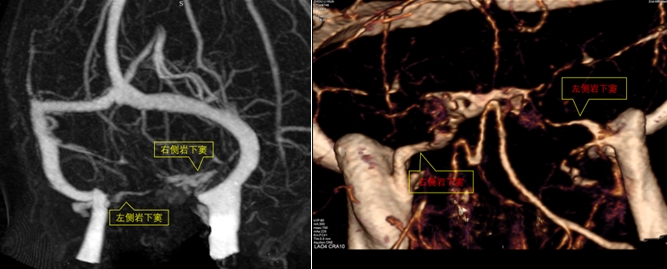

岩下窦是位于颞骨岩部锥体后面下缘的岩枕裂内的硬脑膜窦。前通海绵窦,在颈静脉孔处注入颈静脉上球或乙状窦。岩下窦内血液主要由脑垂体回流,在该处采集血样标本,可直接反映出垂体激素的输出情况,通过比较岩下窦与外周静脉血的促肾上腺皮质激素(ACTH)水平,可以为库欣综合征做出精准的病因学诊断。

为了做出明确的诊断,对病灶进行精准定位,岩下窦采血势在必行;为此张利莉副主任医师多次与神经外科蒋永祥副主任医师会诊讨论检查方案;两个科室经会诊商议决定,由神经外科操作将采血的导管置入双侧岩下窦,岩下窦采血的难点在于岩下窦存在一定的解剖变异或者发育异常,导致导管置入困难。随后完善的头 CTV检查发现患者左侧岩下窦纤细,存在发育变异,但经神经外科评估后,发育变异虽然增加了置管的难度,但仍在可控范围内。